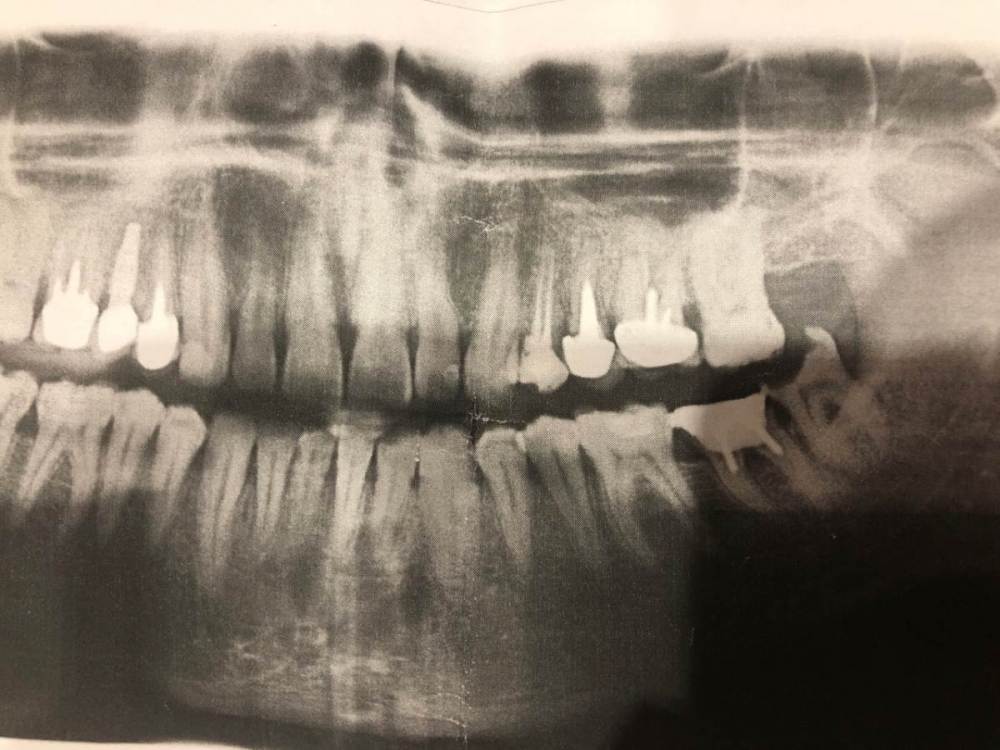

denisss88 Опубликовано 30 октября, 2023 Поделиться Опубликовано 30 октября, 2023 (изменено) Здравствуйте! Откололась пломба на левой 8ке, пошел удалять. Но хирург сказала, что лучше мне его спасать, так как с 7кой проблемы, типа коронку на нее не поставишь уже (права или нет?) И по ее мнению, 8 надо оставить для моста в будущем. Есть 2 снимка с разницей в 3 года, деградации вроде не видно Изменено 30 октября, 2023 пользователем denisss88 Ссылка на комментарий